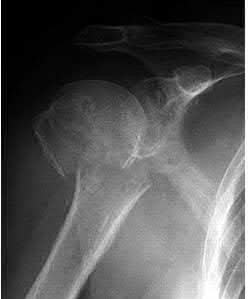

A 44-year-old male is struck by a vehicle while riding his bike. In the trauma bay, he complains of right shoulder pain . Upper extremity physical exam reveals no neurologic deficits, and an initial radiograph of the shoulder is shown in Figure A. A CT scan of the shoulder shows 1cm of posterior displacement of the tuberosity fragment. Which of the following is true regarding this injury?

The radiograph in Figure A demonstrates a posteriorly displaced greater tuberosity fracture. These injuries are often associated with anterior shoulder dislocations, and concomitant rotator cuff tears. The subscapularis attaches to the lesser tuberosity, and is not a deforming force. Open reduction and internal fixation (ORIF) is usually the treatment of choice, and it is well accepted that more than 5mm of displacement is an indication for surgery in patients that require overhead function of the arm.

Flatow et al evaluated 12 patients who were an average of five years status post ORIF of displaced greater tuberosity fractures. All fractures healed without postoperative displacement. Six patients had an excellent result and six had a good result.

Platzer et al retrospectively analyzed functional and radiographic results of 52 patients with operative treatment of displaced greater tuberosity fractures at an average time of 5.5 years from surgery compared to 9 patients with equivalent injuries treated non-operatively. Evaluation of the results of the surgical study group and the nonoperative control group, patients with reduction and fixat ion of greater tuberosity fractures had significantly better

results on shoulder function than did those with conservative treatment.